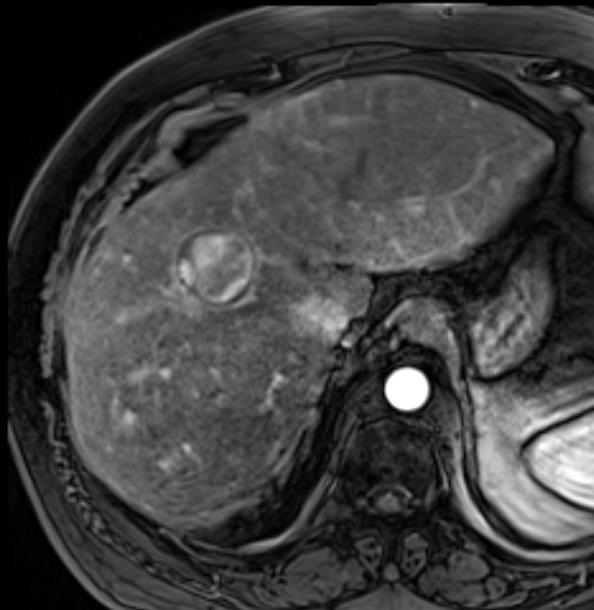

Exploiting [ɪksp'lɔɪtɪŋ] that data, we prospectively [prəs'pektɪvlɪ] evaluated technical efficacy [ˈefɪkəsi] of balloon micro-catheter assisted drug eluting beads trans-arterial chemoembolization (BDEB-TACE) in the treatment of hepatocellular carcinoma (HCC) in this pilot study.

• The Modified Response Evaluation Criteria in Solid [ˈsɑlɪd Tumours (mRECIST) guideline was utilized as a benchmark for interpreting follow-up imaging performed 4-6 weeks after BDEB-TACE.

Initial results by including use of occlusive balloon micro-catheter in DEB-TACE, where there is a significant arterial stump pressure difference showed impressive [ɪmˈpresɪv] radiological responses. However further research is required in this nascent [ˈnæsnt] therapy.